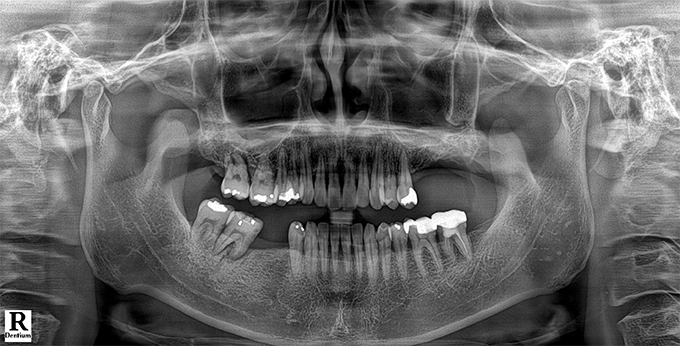

Before & After

임플란트 전후사진

before

2022.10.24

After

2022.11.01

※ 상기 치료전후 사진은 환자의 동의 하에 게재되는 것이며 동일한 촬영각도로 촬영 하였고 치료 기간을 명시하였습니다.

이러한 치료의 결과는 이 환자분에게만 해당되는 것이며 환자의 상태에 따라 똑같은 결과를 얻지 못할 수도 있습니다.

환자분의 상태에 따라 치료 기간, 효과 및 부작용은 상이할 수 있습니다.

치료전후 사진 게재는 의료법 제 23조, 제56조에 의거하여 게재합니다.